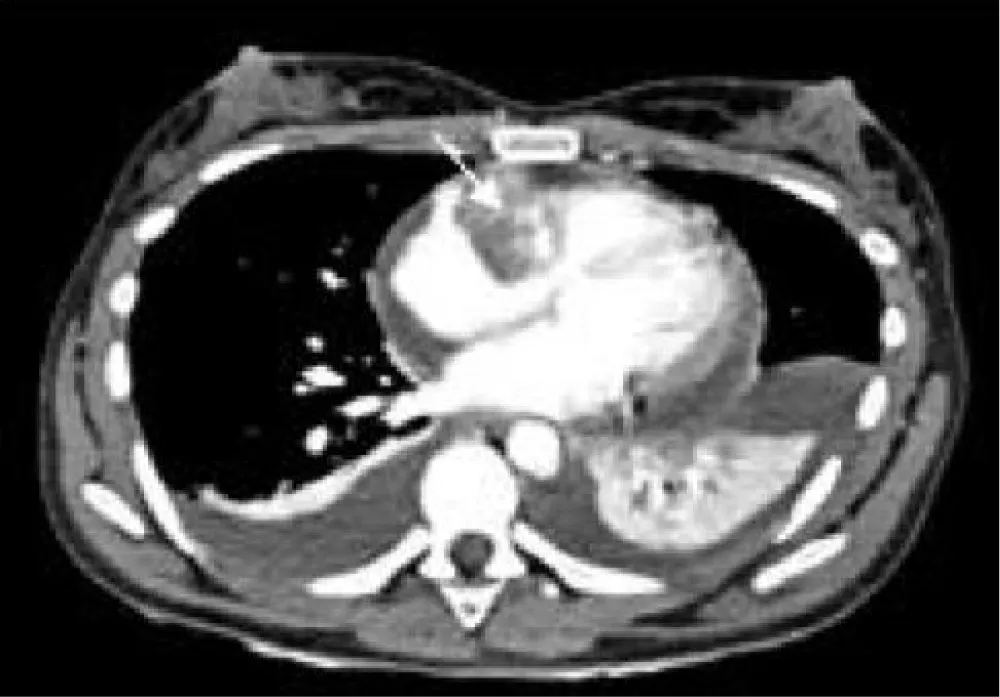

To better delineate and characterize the cardiac mass, a chest CT was performed (Figure 1). This examination revealed moderate pericardial effusion with the existence of a low attenuation mass in the right atrium, extending along the pericardium with heterogeneous enhancement, of approximately 3.5 cm, which corresponds to a cardiac tumor. Cardiac magnetic resonance imaging (Figure 2) exposed a cardiac mass at the level of the right atrium with extension into the pericardium and free wall of the right ventricle and heterogeneous late enhancement, being hypointense on T1 and T2, This is not the most typical pattern, which usually consists of low signal T1-weighted sequences, and increased signal and central areas of hyperintensity on T2weighted, consistent with hemorrhage and necrosis, and areas of moderate signal intensity in more peripheral regions [3]. Because of their high vascularity, strong signal enhancement is seen after the administration of IV gadolinium [3]. However, given the propensity of angiosarcomas to necrosis and hemorrhage, these often have heterogeneous signals on cardiac MR images [3]. Fluorodeoxyglucose-18 combined with positron emission tomography/computed tomography (18F-FDG-PET/CT) (Figure 3) confirmed pathological metabolic activity in the recognized mass in the right atrium extending along the pericardium with intensely increased FDG uptake (SUVmax) of 17.3. Moderate Pericardial effusion was noted and multiple hypermetabolic foci in the bodies of the D12, L2, and L3 vertebrae, as well as in the proximal third of both femurs, without evidence of structural lesions on CT with SUVmax of 6.9.

Download Image

Figure 1: Arterial phase chest CT. Findings: Right atrial mass with heterogeneous centripetal enhancement (arrow) and pericardial effusion.